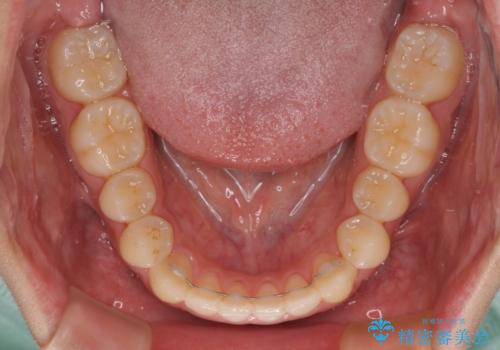

- 前歯のデコボコを治したいとのことで来院された患者様です。

受け口傾向の骨格であり、前歯はクロスバイトまたは切端咬合となっており、叢生は警備であったため、下顎を中心に歯列全体の後方移動を行い、IPR(歯と歯の間を削る)によってデコボコが解消するように設計し、インビザラインにより治療を行うこととしました。

受け口傾向のインビザライン矯正は比較的治療を行いやすいため、きれいに仕上げることができました。舌の突出癖が顕著であったため、改善のためのトレーニングをしっかりと行っていただきました。